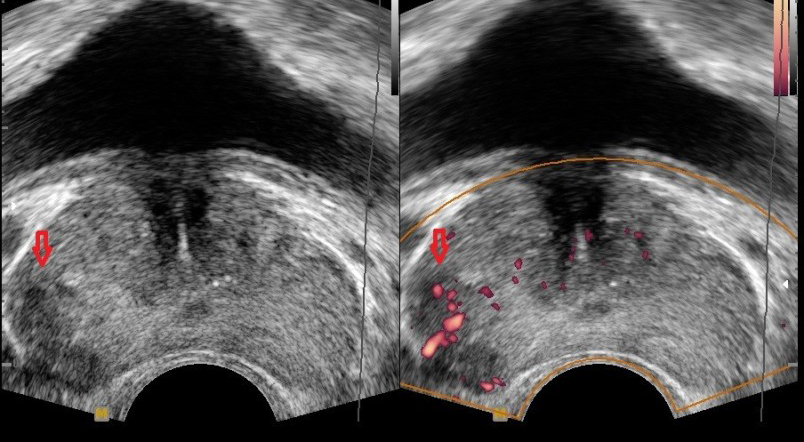

남자의 건강을 위협하는 대표 질병 중 한 가지는 전립선 질병이다. 전립선염은 남자의 50%가 일생에 한 번은 겪어볼 정도로 흔한 질병이 됐으며, 전립선암은 최근 20년간 20배 넘게 증가할 정도로 대중적인 질환이 되었는데요.